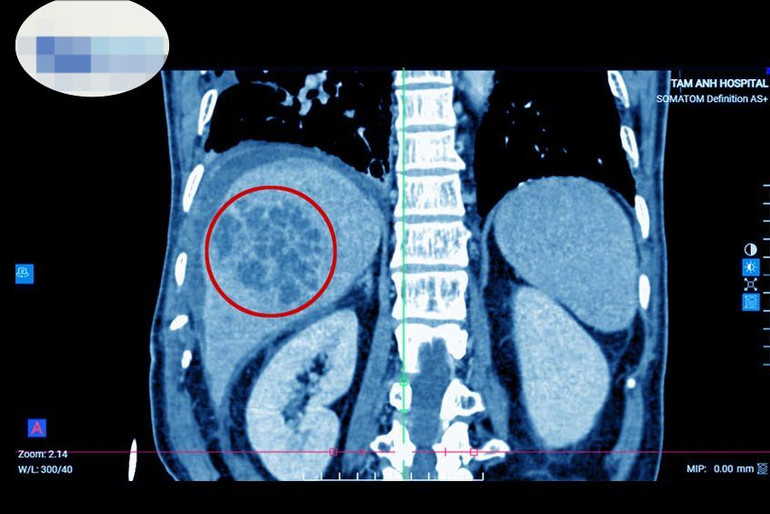

| Hình ảnh ổ áp xe lớn (vùng khoanh đỏ), chiếm gần hết lá gan. |

Bệnh nhân nam 71 tuổi, quê Nam Định đến khám tại Bệnh viện đa khoa Tâm Anh Hà Nội trong tình trạng sốt cao, đau bụng hạ sườn phải. Thạc sĩ, bác sĩ Phạm Khắc Khiêm, khoa Tiêu hóa cho biết, kết khám lâm sàng kết hợp cận lâm sàng như siêu âm, chụp cắt lớp vi tính phát hiện bệnh nhân có ổ áp xe ở gan phải, kích thước lớn khoảng 7*8cm. Quá trình hỏi bệnh được biết người bệnh có thói quen ăn gỏi cá nhiều năm nay. Xét nghiệm có kháng thể sán lá gan nhỏ, cấy mủ áp xe phát hiện vi khuẩn E.coli.